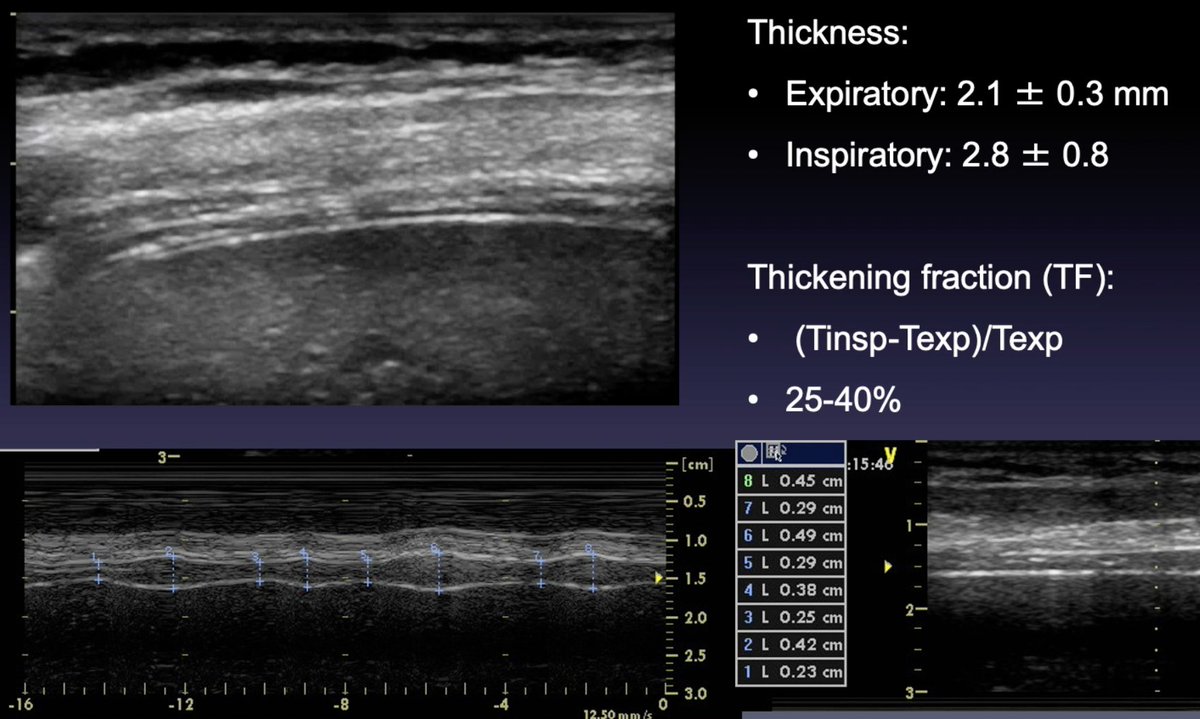

Diaphragm #POCUS assess

➡️excursion = displacement during inspiratory effort (affected by P on MV) + inspiratory/expiratory times (use anatomical M-Mode to align with direction of diaphragm excursion)

➡️thickness = variation during respiratory cycle + TF

🧵 Mongodi S #eSMART2021